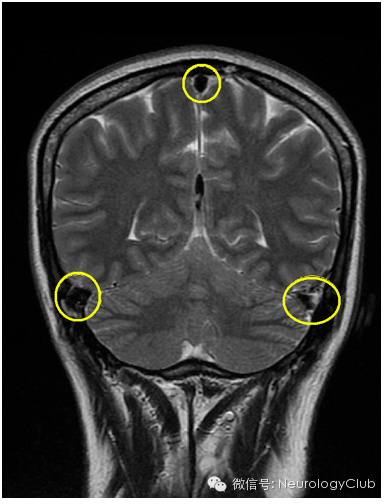

硬膜下积液表现为双侧对称性薄层积液,无占位效应,对下面的脑沟脑裂无压迫效应。

(3)静脉结构充盈(Engorgement of venous structures)

(静脉窦扩张变圆)

(5)脑组织下沉(Sagging of the brain)